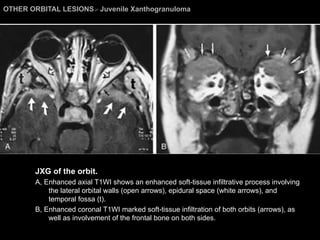

OTHER ORBITAL LESIONS >  Juvenile Xanthogranuloma JXG of the orbit.  A, Enhanced axial T1WI shows an enhanced soft-tissue infiltrative process involving the lateral orbital walls (open arrows), epidural space (white arrows), and temporal fossa (t).  B, Enhanced coronal T1WI marked soft-tissue infiltration of both orbits (arrows), as well as involvement of the frontal bone on both sides.